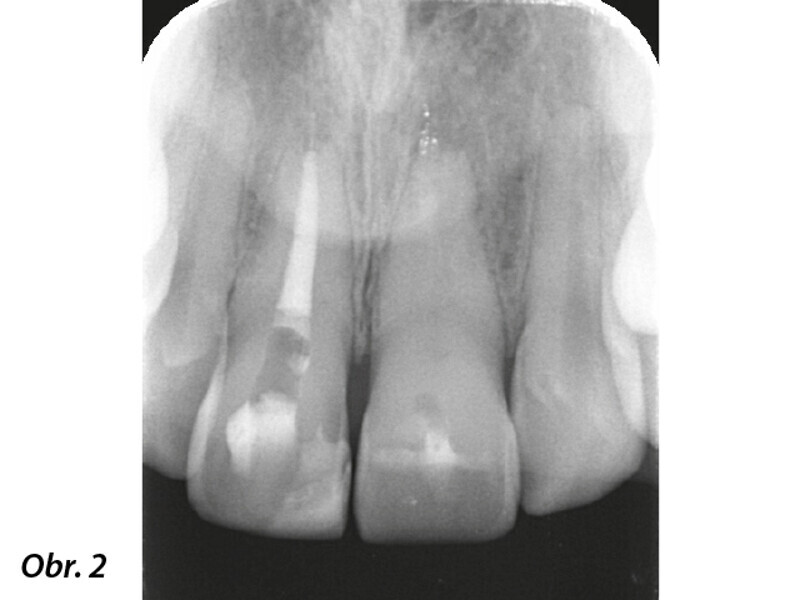

Navigovaný endodontický přístup u kalcifikovaných frontálních zubů: Kazuistika